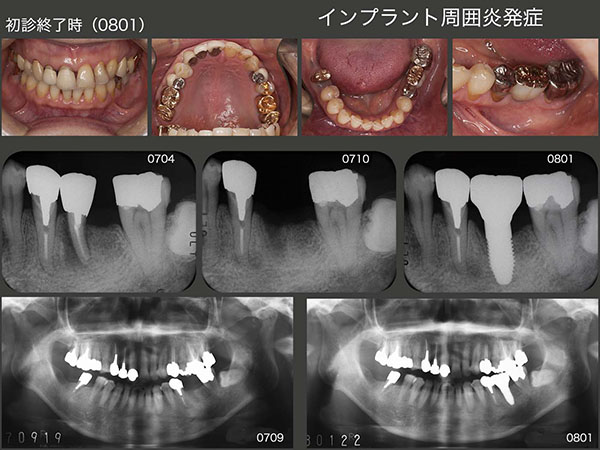

2.インプラント周囲炎発症

1994年11月初診,当時47歳の女性.2007年5月に左下6の近心根を歯根破折にて抜去した.そして,11月に直径5mm,長さ10mmのインプラントを植立した.スライド上段右端に08年1月,硬質レジン前装冠装着時を示す.今になって思うと,顎堤の近遠心的な距離があるので直径5mmを選択したが,頰舌側の距離がないことから,骨の水平的拡大が必要,あるいはこのサイズのインプラントの適応症ではなかったと反省している.そのためか,数年後にインプラント周囲炎が発症してしまった.

2014年10月までインプラントの経過をみていたが,この時点で歯周ポケットが最大8mmとなったため,フラップを開け,中の掻爬を行った.しかしその後も改善せず,16年9月に硬質レジン前装冠を外し,再度掻爬を行った.清掃しやすい環境にして3ヵ月経過をみたが,まだ改善傾向を示さなかった.そこで12月にまず頰小帯を切除し,その後に掻爬術を施す治療計画を立て,患者さんに協力頂けるようお願いしてみた.快諾を得,背水の陣で3回目の掻爬を17年1月に行った.歯周ポケットは唇側でまだ5mm残っているが,歯肉の状態は改善した.6月,インプラントをロスしても対応できるように可撤式の補綴装置を装着した.

この患者さんは右咬みなのか,2015年7月に5mmであった右上5の歯周ポケットが16年2月には9mmと,歯周病が急に悪化した.そこで仕方なく右上5の抜髄を行い,自然挺出を行った.8月まで3ヵ月間挺出したのち,同月歯周外科処置を行った.歯周ポケットは3mm以下に改善したが,歯の動揺が残ったため,右上4と連結固定した.

右下には,右下6,7それぞれの遠心根を支台歯としたブリッジを装着していたが,06年に右下7の遠心根が保存困難となり抜去した.その後,右下6の遠心根は孤立歯の状態のまま10年が経過した.右側の大臼歯部の咬合接触面積が少ないことが,右上5の悪化に繋がったと反省し,今回は右下大臼歯部もしっかり咬合させることにした.まず,右下6の遠心根をアップライトし,歯軸を改善したのち,コーヌス義歯を装着した.